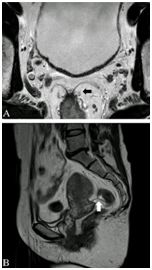

图10  61岁男性直肠癌,轴位T2加权像显示直肠肿物(星号),左侧直肠系膜EMVI(箭头),右侧直肠系膜淋巴结受累(长箭头),CRM侵犯。

图11  61岁男性直肠癌,轴位T2加权像显示直肠前壁锯齿状肿瘤,CRM侵犯(长箭头)。直肠前壁与直肠系膜筋膜非常接近,前壁直肠肿瘤CRM 阳性可能性较高。

8.下位直肠癌和肛管癌

下位直肠腺癌位于肛管5cm内,肿瘤在耻骨直肠肌/韧带水平或之下时应格外关注,因为距离肛管扩约肌很近。低位直肠癌距离CRM很近,增加复发风险。鉴别低位直肠癌与肛管癌很具挑战性,AJCC推荐肿瘤表面中心超过齿状线2cm以上为下位直肠癌(图12),不足2cm时为肛管癌。不过齿状线在MRI并不直接可见,大致相当于外扩约肌最上端或直肠下端,冠状面可通过肛提肌明确,肛提肌形成了坐骨直肠窝的顶。

图12低位直肠癌,冠状面T2加权像显示左下直肠齿状线上(长箭头)分叶状肿物(箭头)。齿状线相当于肛提肌水平,插入图像显示侵肿瘤犯左耻骨直肠肌或韧带(长箭头)